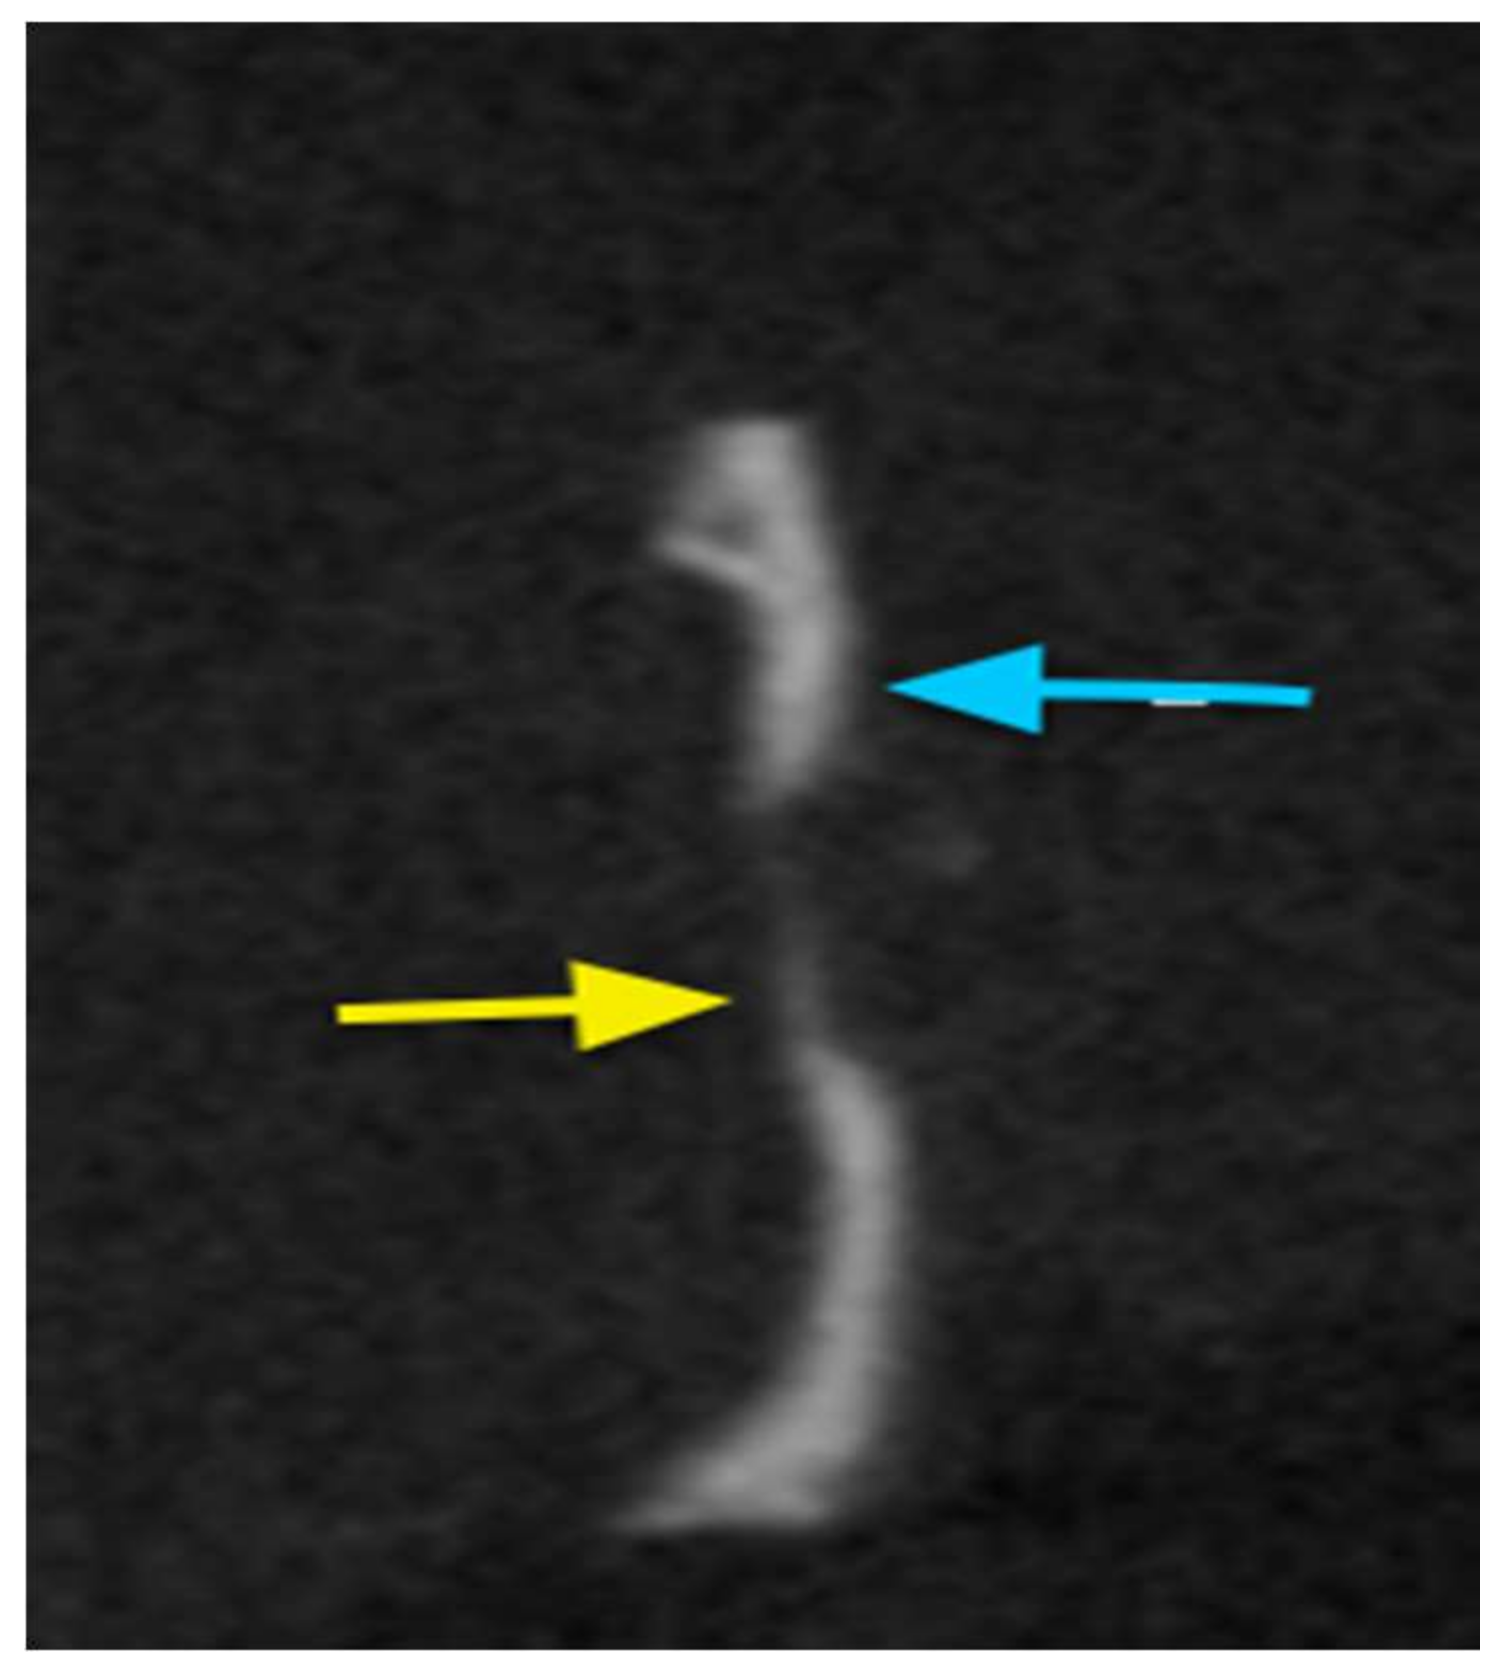

2.7.2. Cone Beam Computed Tomography (CBCT)

Cone Beam Tomography